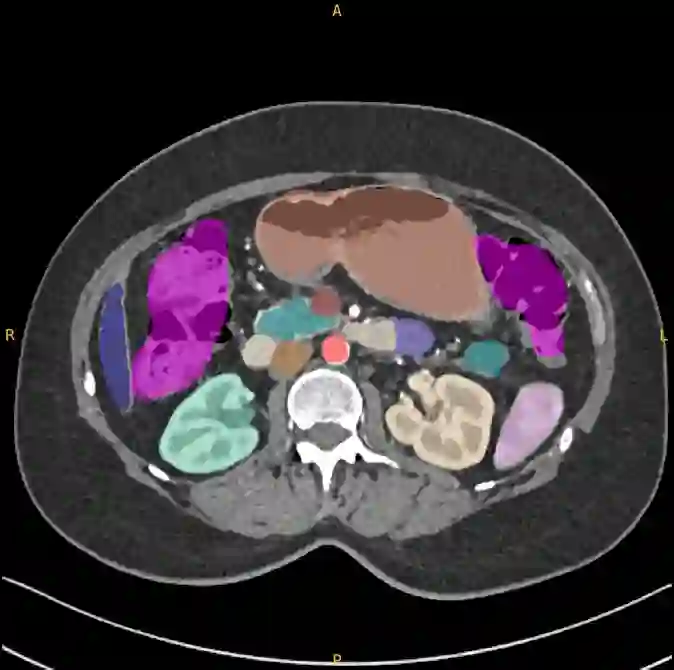

Pancreatic ductal adenocarcinoma (PDAC), one of the deadliest solid malignancies, is often detected at a late and inoperable stage. Retrospective reviews of prediagnostic CT scans, when conducted by expert radiologists aware that the patient later developed PDAC, frequently reveal lesions that were previously overlooked. To help detecting these lesions earlier, we developed an automated system named ePAI (early Pancreatic cancer detection with Artificial Intelligence). It was trained on data from 1,598 patients from a single medical center. In the internal test involving 1,009 patients, ePAI achieved an area under the receiver operating characteristic curve (AUC) of 0.939-0.999, a sensitivity of 95.3%, and a specificity of 98.7% for detecting small PDAC less than 2 cm in diameter, precisely localizing PDAC as small as 2 mm. In an external test involving 7,158 patients across 6 centers, ePAI achieved an AUC of 0.918-0.945, a sensitivity of 91.5%, and a specificity of 88.0%, precisely localizing PDAC as small as 5 mm. Importantly, ePAI detected PDACs on prediagnostic CT scans obtained 3 to 36 months before clinical diagnosis that had originally been overlooked by radiologists. It successfully detected and localized PDACs in 75 of 159 patients, with a median lead time of 347 days before clinical diagnosis. Our multi-reader study showed that ePAI significantly outperformed 30 board-certified radiologists by 50.3% (P < 0.05) in sensitivity while maintaining a comparable specificity of 95.4% in detecting PDACs early and prediagnostic. These findings suggest its potential of ePAI as an assistive tool to improve early detection of pancreatic cancer.

翻译:胰腺导管腺癌(PDAC)作为致死率最高的实体恶性肿瘤之一,常在晚期且无法手术的阶段才被检出。回顾性分析诊断前的CT扫描时,若由知晓患者后续确诊PDAC的资深放射科医师审阅,常可发现先前被忽略的病灶。为助力更早发现这些病灶,我们开发了一套名为ePAI(基于人工智能的早期胰腺癌检测)的自动化系统。该系统使用来自单一医疗中心的1,598名患者数据进行训练。在包含1,009名患者的内部测试中,ePAI在检测直径小于2厘米的小型PDAC时,受试者工作特征曲线下面积(AUC)达0.939-0.999,灵敏度为95.3%,特异度为98.7%,并能精确定位小至2毫米的PDAC。在涵盖6个中心、7,158名患者的外部测试中,ePAI的AUC为0.918-0.945,灵敏度达91.5%,特异度为88.0%,可精确定位小至5毫米的PDAC。尤为重要的是,ePAI在临床诊断前3至36个月获取、曾被放射科医师漏诊的诊断前CT扫描中成功检测出PDAC。在159名患者中,系统成功检测并定位了75例PDAC,中位领先临床诊断时间达347天。我们的多阅片者研究表明,在早期及诊断前PDAC检测中,ePAI的灵敏度显著优于30名具备执业资格的放射科医师50.3%(P < 0.05),同时保持95.4%的可比特异度。这些发现表明ePAI具备作为辅助工具提升胰腺癌早期检测能力的潜力。